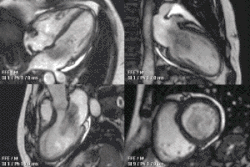

An atrial myxoma may create an extra heart sound, audible to auscultation just after S2. It is most seen on echocardiography, as a pedunculated mass that is heterogeneous in appearance. A left atrial myxoma will cause an increase in pulmonary capillary wedge pressure.

The differential diagnosis include other cardiac tumors such as lipomas and rhabdomyomas (and rarely teratomas). These other tumors of the heart are typically not pedunculated, however, and are more likely to infiltrate the muscle of the heart. Cardiac magnetic resonance imaging (MRI) can help non-invasively diagnose cardiac tumors. However, diagnosis usually requires examination of a tissue sample by a pathologist.